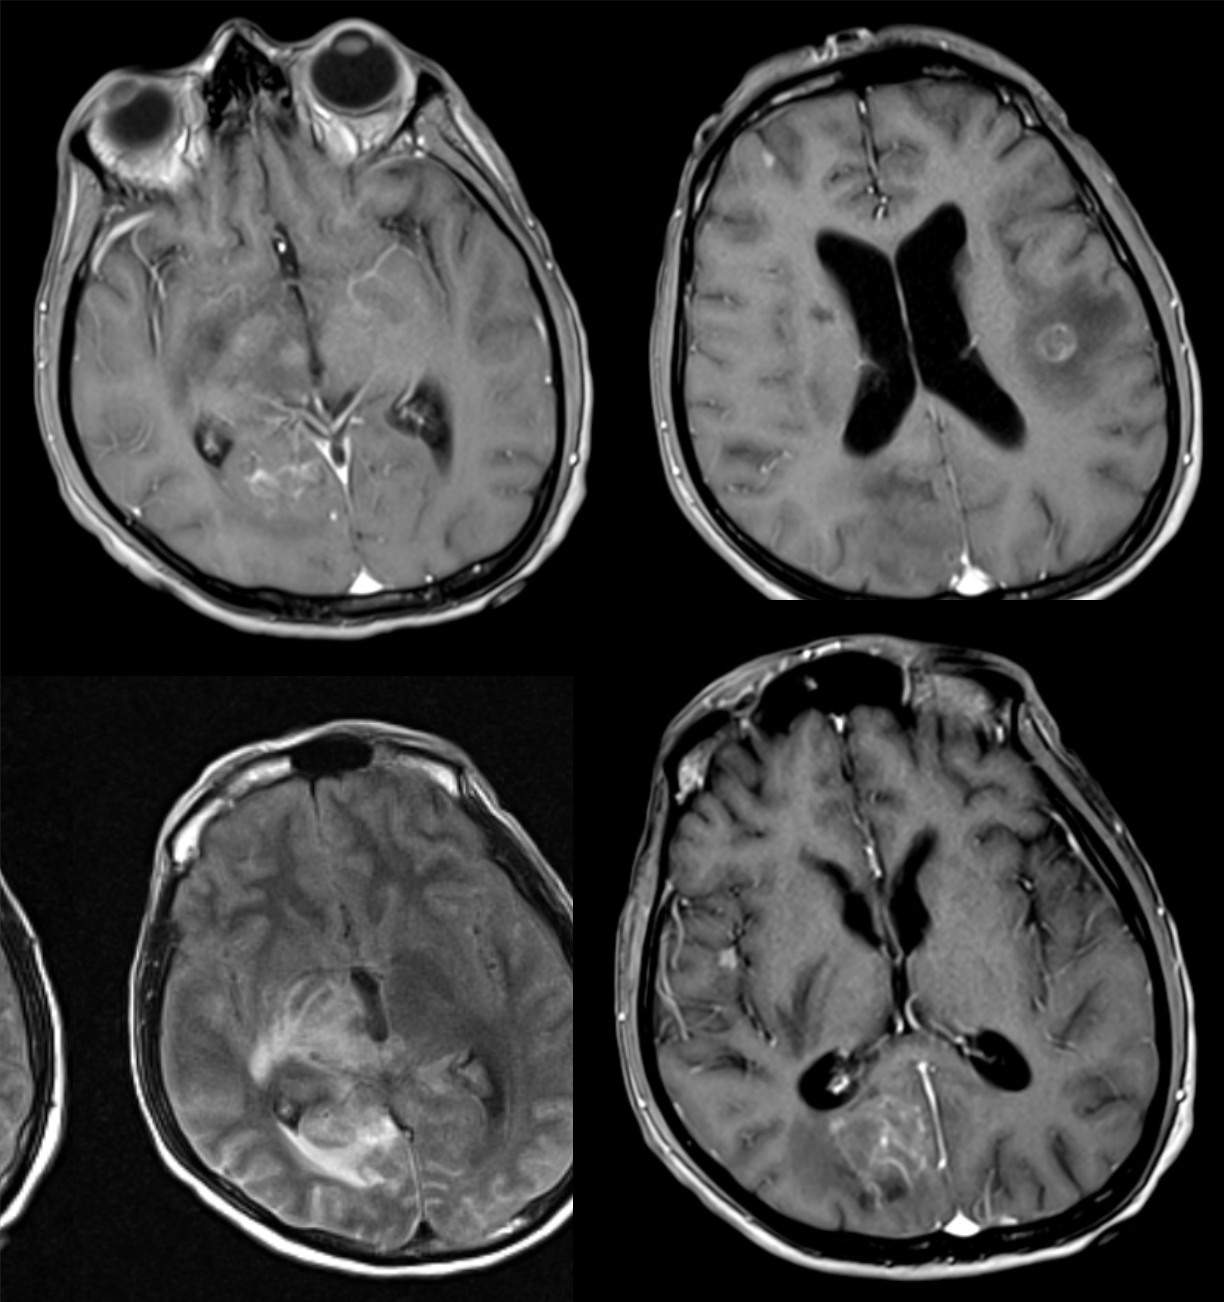

39 y/o M found down.

Intraventricular bleed due to AVM